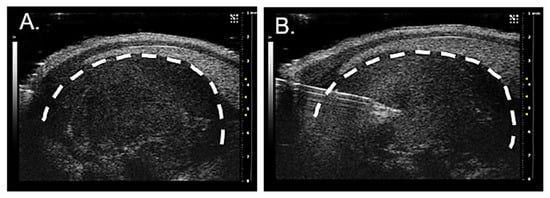

2.6. Ultrasound-Guided Injection of Axonal Tracer and Collection of Peripheral Ganglia